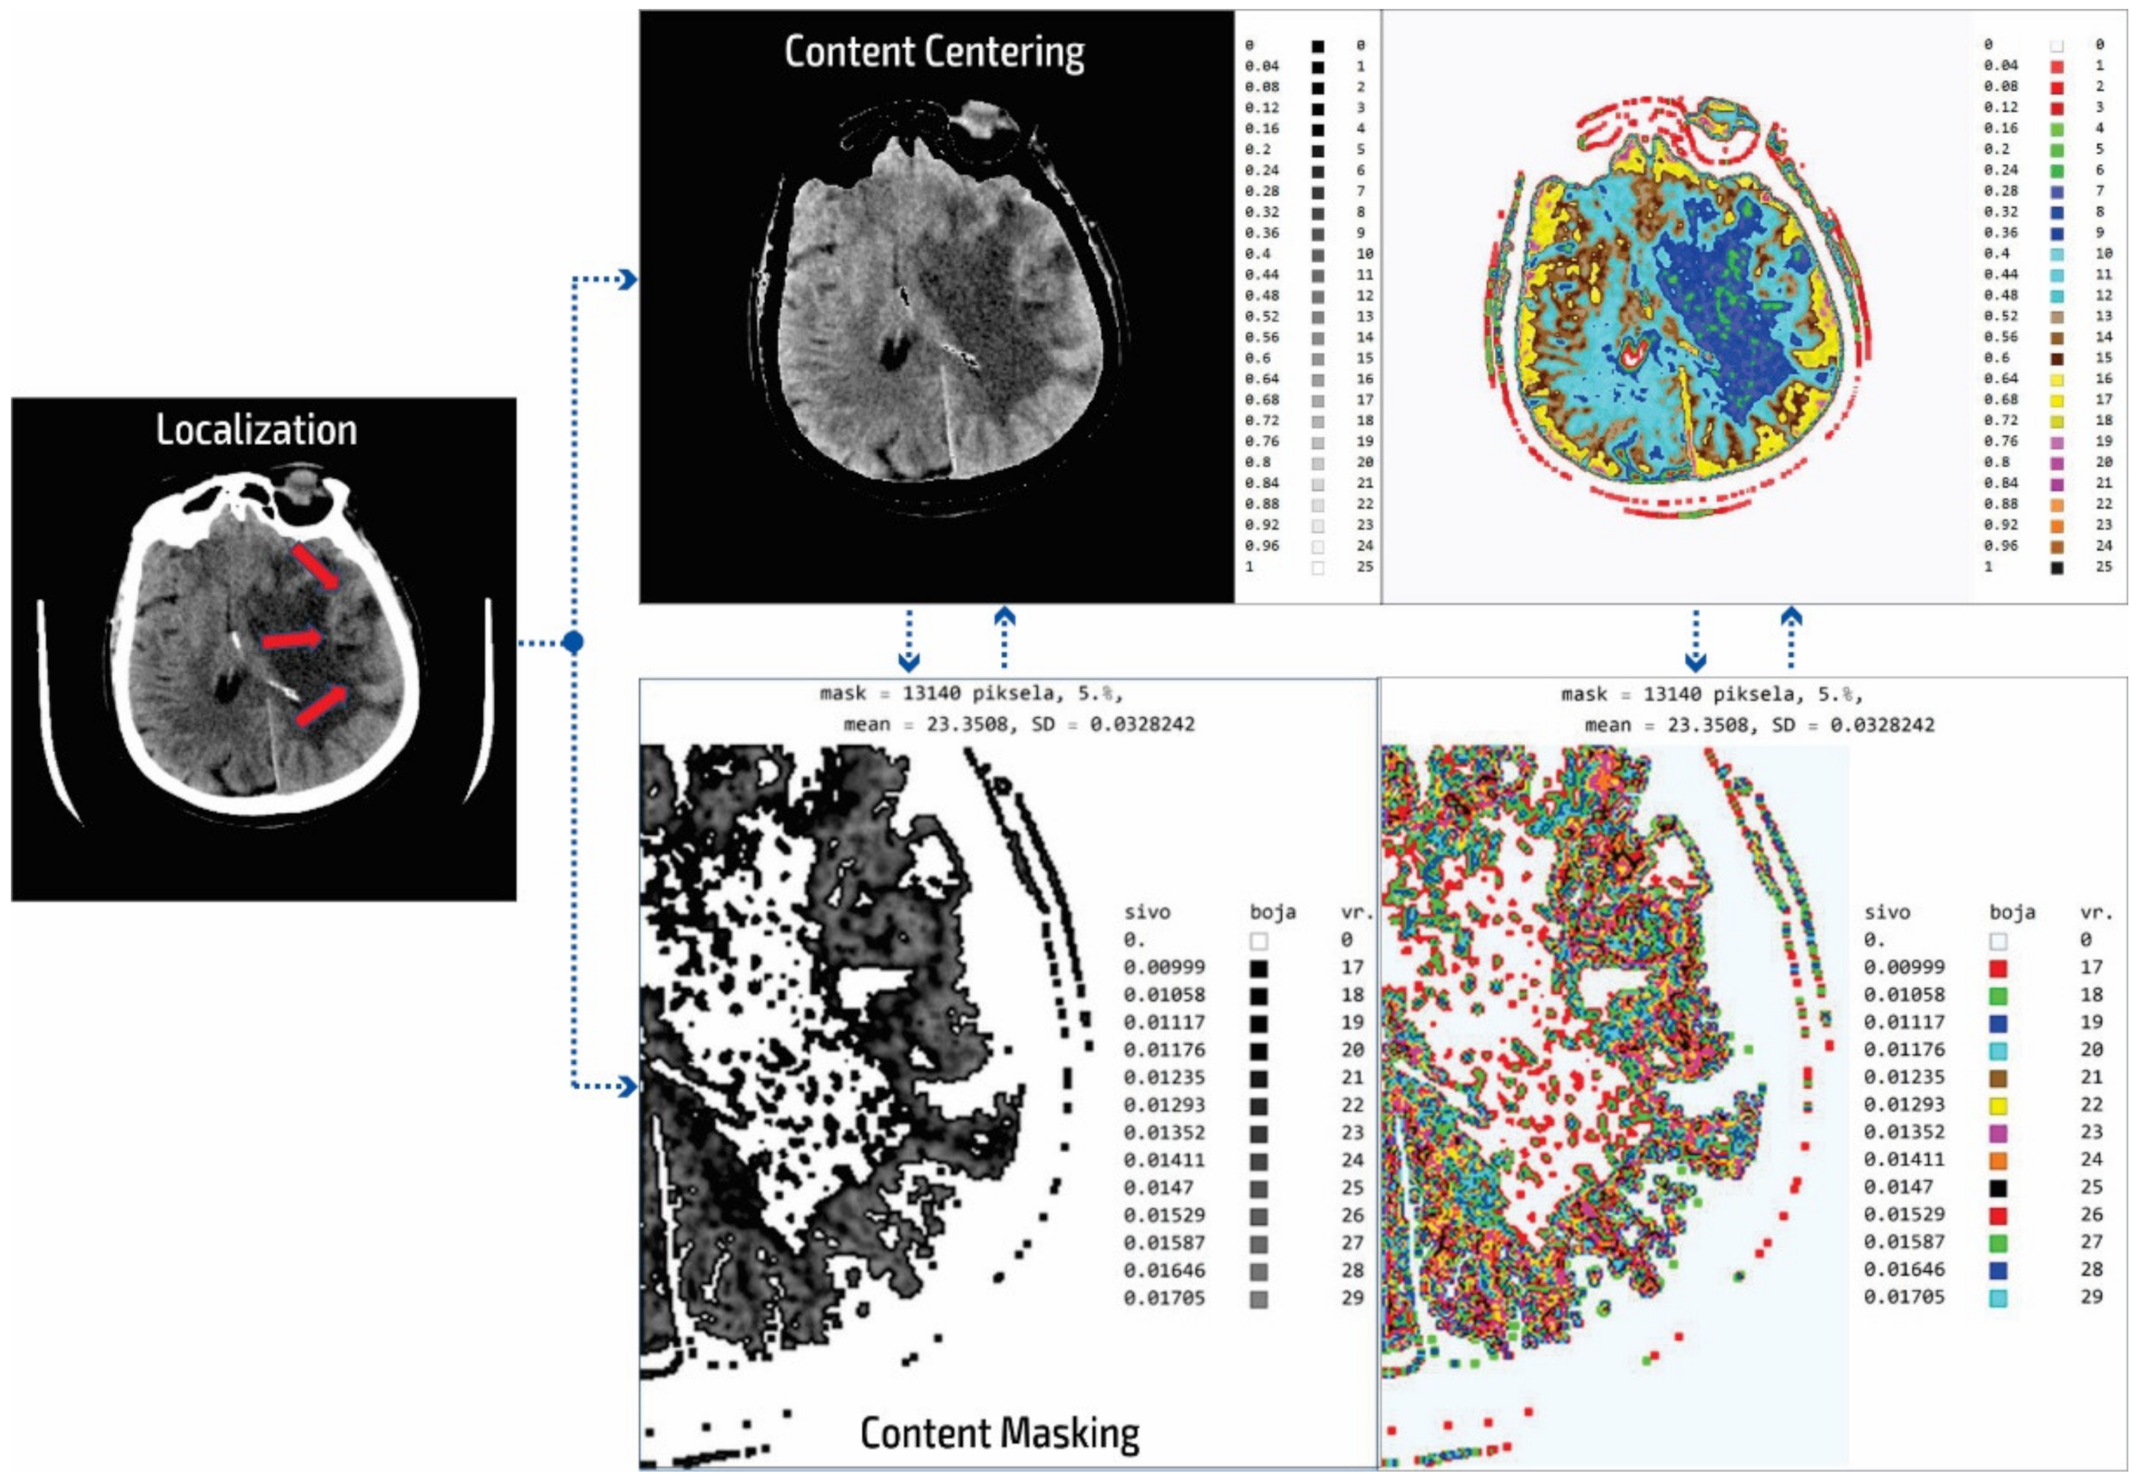

2.2. Smart Visualization Method (SVMI)

3.1. Technological Description